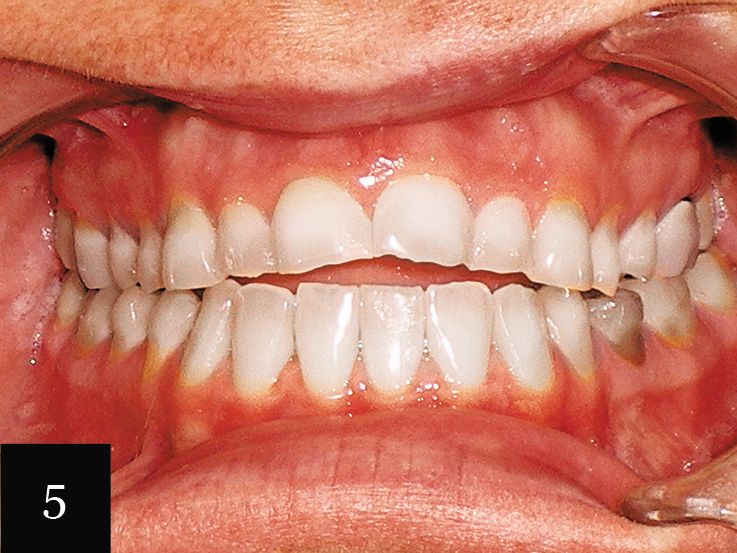

Case No. 2

This case showcases a woman in her mid-30s who had an anterior open bite, as well as a history of bulimia (Figs. 5-6). The eating disorder led to severe wear, which can be seen on the upper arch. The gum line was also very irregular. The impression accurately captured the detail of the teeth and a series of 12 aligners was made.

Following this initial phase, an additional impression was taken for six more aligners. Finally, one more impression was taken with Imprint 3 VPS impression material to create crowns for tooth Nos. 3-14. This treatment significantly elevated the patient’s level of confidence in her smile (Figs. 7 and 8).